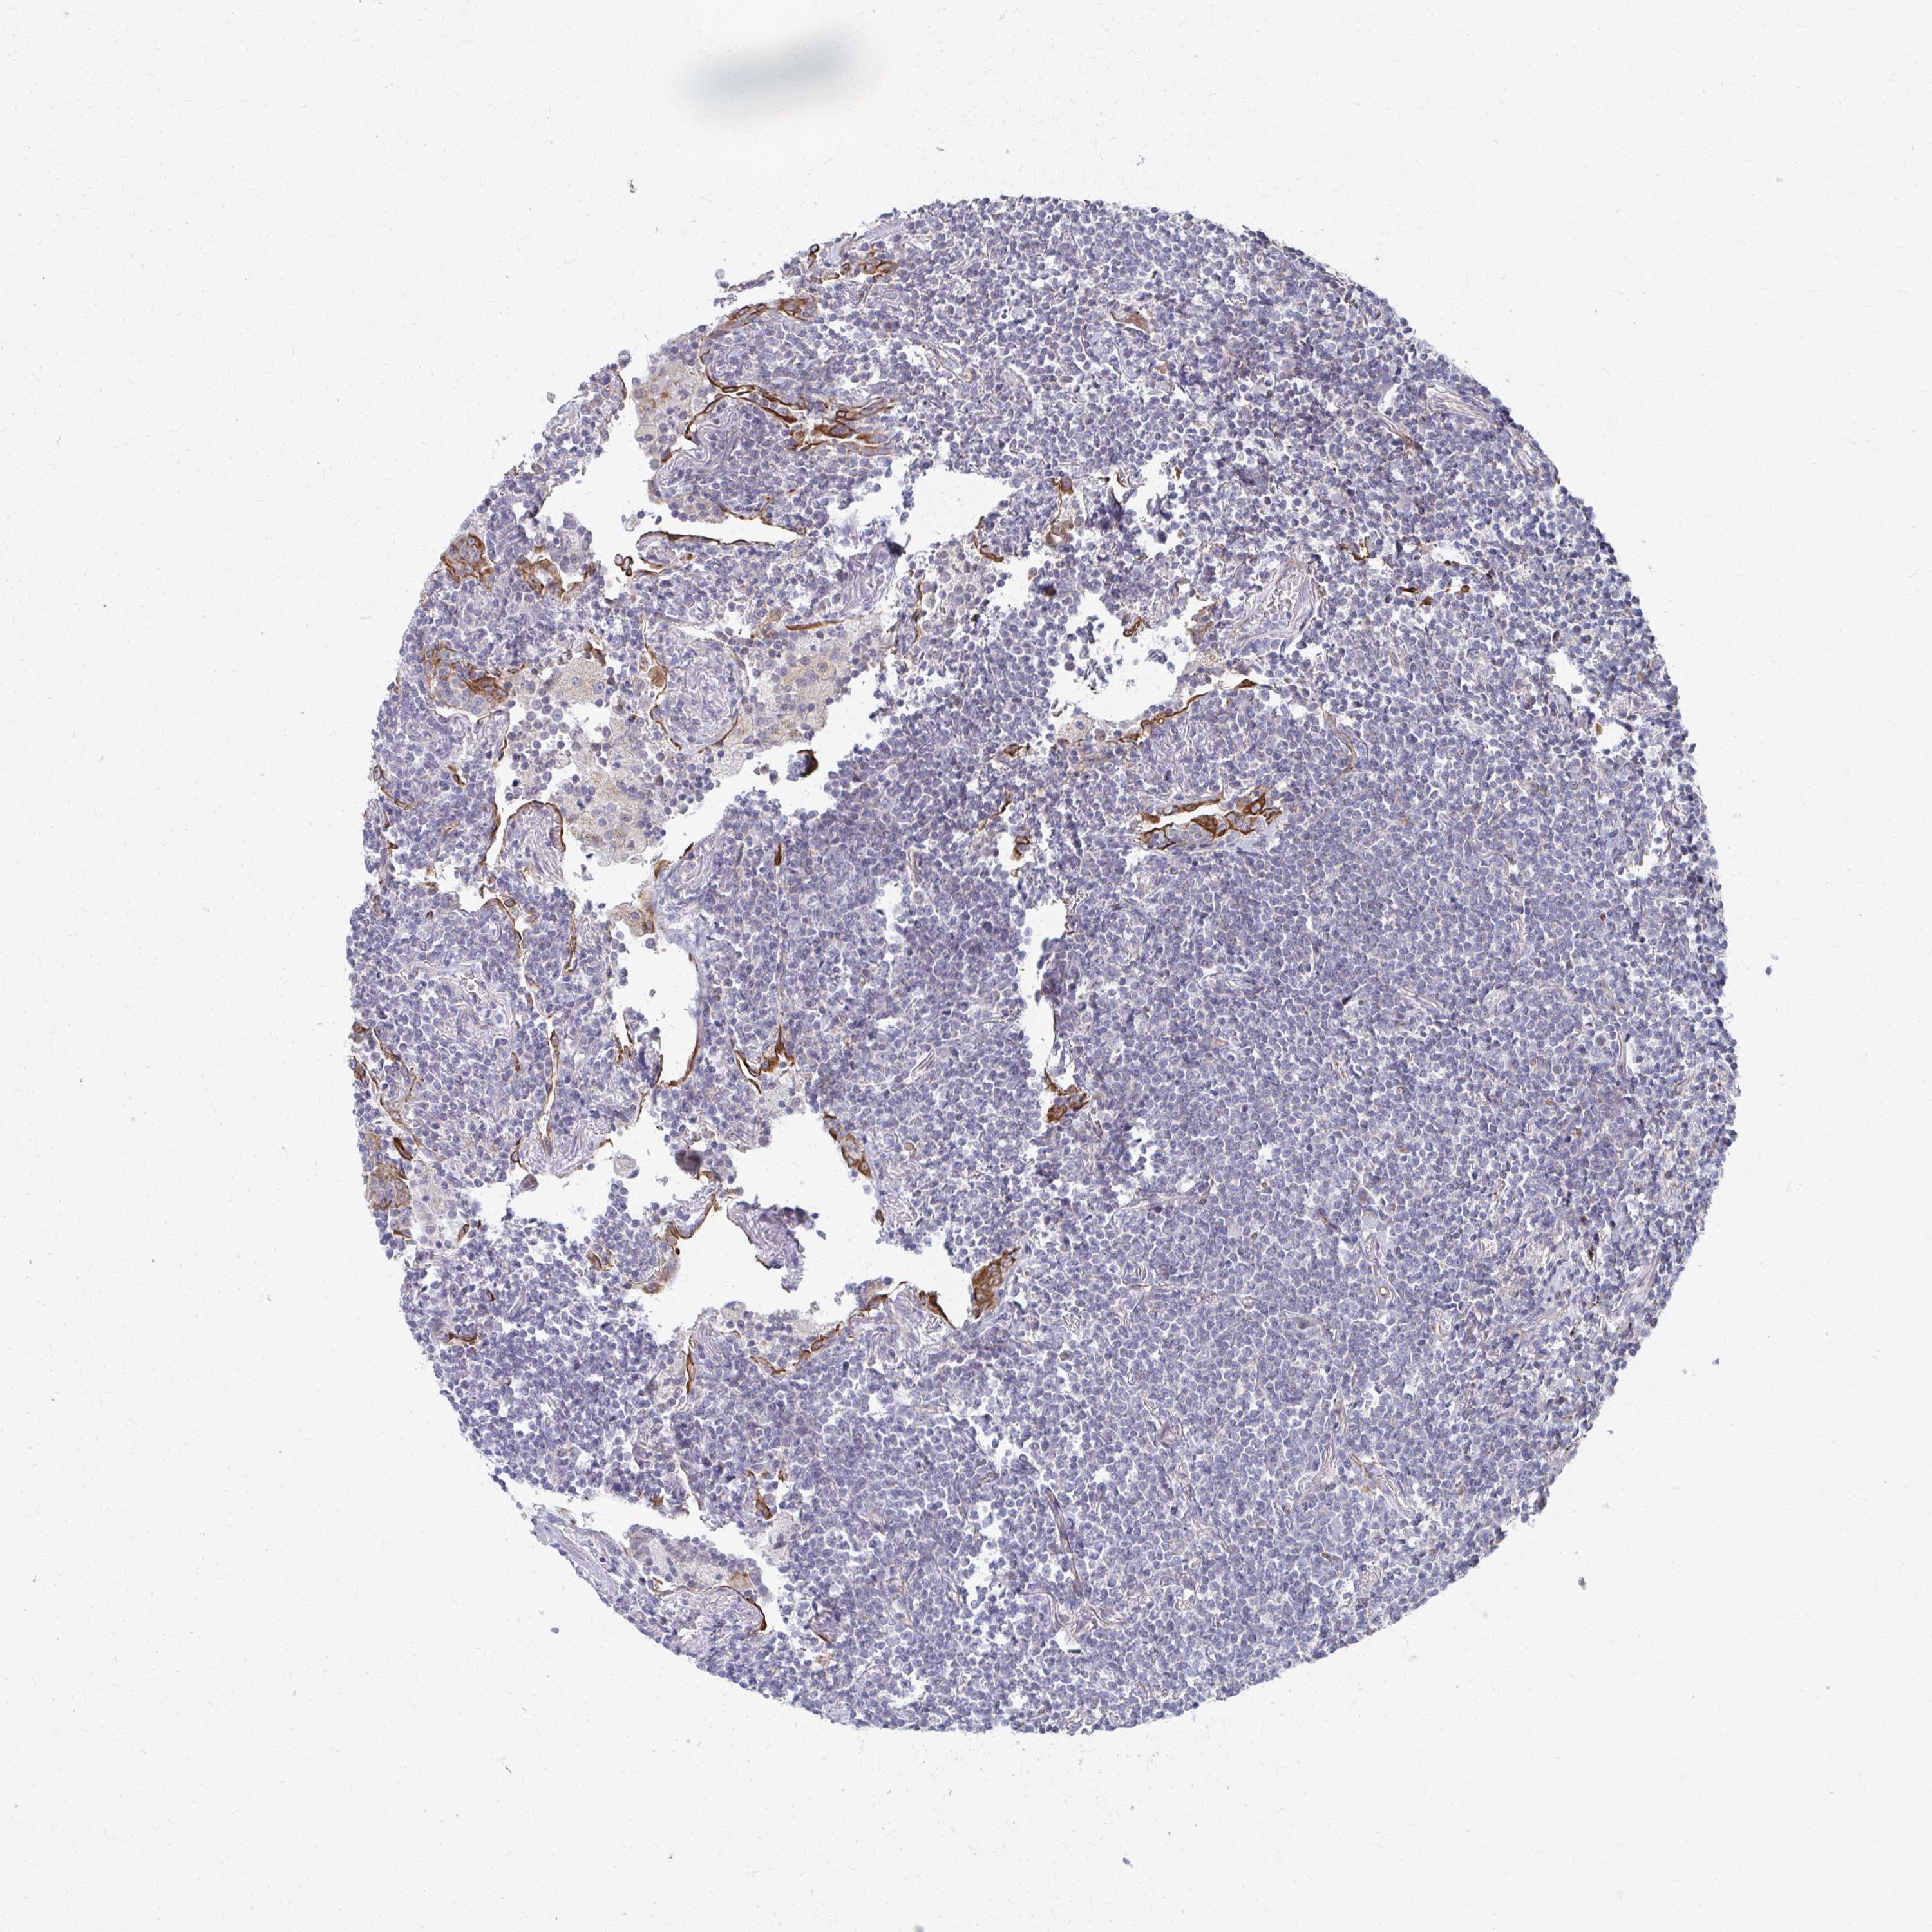

CANCER LYMPHOMA Show tissue menu

LYMPHOMA - Protein expressioni

A mouse-over function shows sample information and annotation data. Click on an image to view it in a full screen mode. Samples can be filtered based on level of antibody staining by selecting one or several of the following categories: high, medium, low and not detected. The assay and annotation is described here.

Antibody stainingi

Antibody staining in the annotated cell types in the current human tissue is reported as not detected, low, medium, or high, based on conventional immunohistochemistry profiling in selected tissues. This score is based on the combination of the staining intensity and fraction of stained cells.

Each image is clickable and will lead to virtual microscopy that enables deeper exploration of all samples and also displays staining intensity scores, fraction scores and subcellular localization as well as patient and tissue information for each sample.

Antibody HPA043226

Malignant lymphoma, non-Hodgkin's type, Low grade

Malignant lymphoma, non-Hodgkin's type, High grade

Hodgkin's disease, NOS